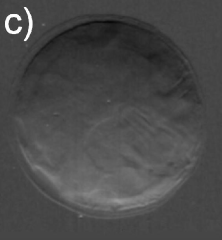

Significant X-ray scattering occurs at the lens surface owing to the air-lens interface. It is responsible for most of the observable features in air exposures, useful to inspect changes in the surface morphology during catarogenesis, as shown in Figs. 1(a) and 1(b) where DEI from healthy and cataractous lenses are compared.

However, to reveal internal density fluctuations the majority of the surface scattering has to be avoided. It is possible by immersing the lens in a medium of nearly the same density of the lens tissue, in this case deionized water. A very clean and uniform image is that obtained in Fig. 1(c) for water exposure of the healthy lens, while large and well defined scattering regions around the nuclei, and also in small amounts at outer regions, are observed in Fig. 1(d) for the cataractous lens.

As summarized in Fig. 2, the image contrast criterions of DEI allows characterization of the scattering properties of the observed internal structures in the lenses. Diffuse-scattering, refraction, and absorption images were collected respectively at the tail (T), shoulder (S), and center (C) of the analyzer window, some good examples are shown in Fig. 3. In the former type of image, the amounts of diffuse-scattering around the internal structures are consistent to the type of scattering expected for an aggregation of tiny precipitates without a well defined boundary, as in Figs. 3(a) and 3(c). On the other hand, refraction images have shown aggregations with dense cores, Fig. 1(d) and 3(d), capable to refract X-rays in an opposite sense of air bubbles, arrow in Fig. 3(f). It indicates that the precipitates are denser than the lens tissue.